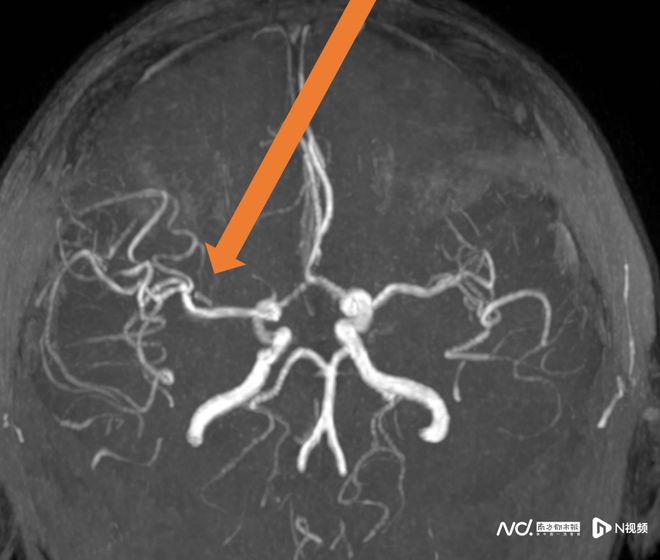

57歲的王阿姨患有風心病,一天吃飯時突然言語不清、左側肢體無力無法站起。家人立即撥打120,經卒中綠色通道確診為右大腦中動脈閉塞,隨即進行靜脈溶栓。

卒中發病呈現年輕化趨勢這個放松動作可能“按”出腦卒中(圖3)

卒中發病呈現年輕化趨勢這個放松動作可能“按”出腦卒中(圖4)